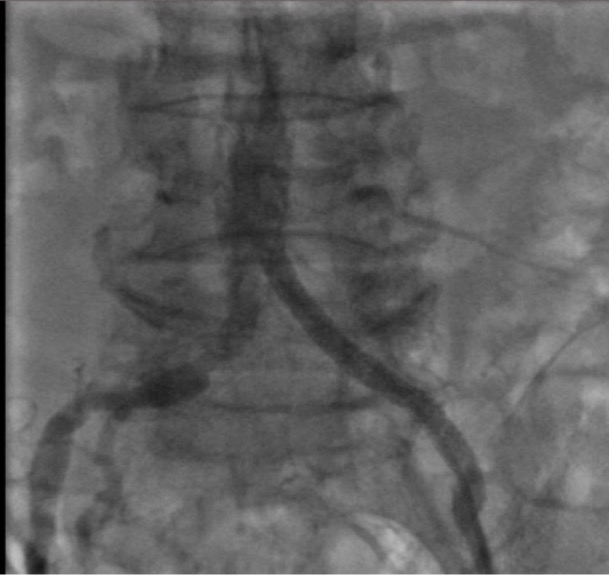

Kết quả CTA cho thấy tắc động mạch chậu bên trái, tắc 1/3 giữa động mạch đùi bên trái và xơ vữa rải rác các động mạch chi dưới khác. Trước tình trạng tổn thương phức tạp này, các bác sĩ chỉ định can thiệp nội mạch (Endovascular Intervention) để kịp thời tái thông các mạch máu bị tắc gồm động mạch chậu và động mạch đùi nông bên trái.

Nhờ ứng dụng kỹ các kỹ thuật can thiệp nâng cao và sự thành thạo trong kinh nghiệm của ekip, ca phẫu thuật đã diễn ra thành công. Bệnh nhân được nong bóng và đặt 1 Stent 06x58mm vào động mạch chậu trái và nong bóng động mạch đùi nông bên trái.

Để điều trị thương tổn hẹp, tắc động mạch chi dưới, can thiệp nội mạch đã được chứng minh có tỷ lệ thành công không kém phẫu thuật làm cầu nối, đặc biệt với những tổn thương tầng trên gối. Ngoài ra, so với phẫu thuật, can thiệp nội mạch có một số ưu điểm sau: Gây tê tại chỗ cho phép thực hiện trên bệnh nhân có nguy cơ cao với gây mê toàn thân; tránh được cuộc mổ lớn, bệnh nhân có thể trở lại hoạt động bình thường trong khoảng 24-48 giờ.

Sau can thiệp, mạch đùi, mạch khoeo và động mạch chày trước, sau của bệnh nhân nảy rõ, chân ấm, giảm đau chân. Mặc dù tình trạng được cải thiện đáng kể, bệnh nhân vẫn được chỉ định tiếp tục điều trị nội khoa tối ưu và tái khám theo dõi định kỳ.